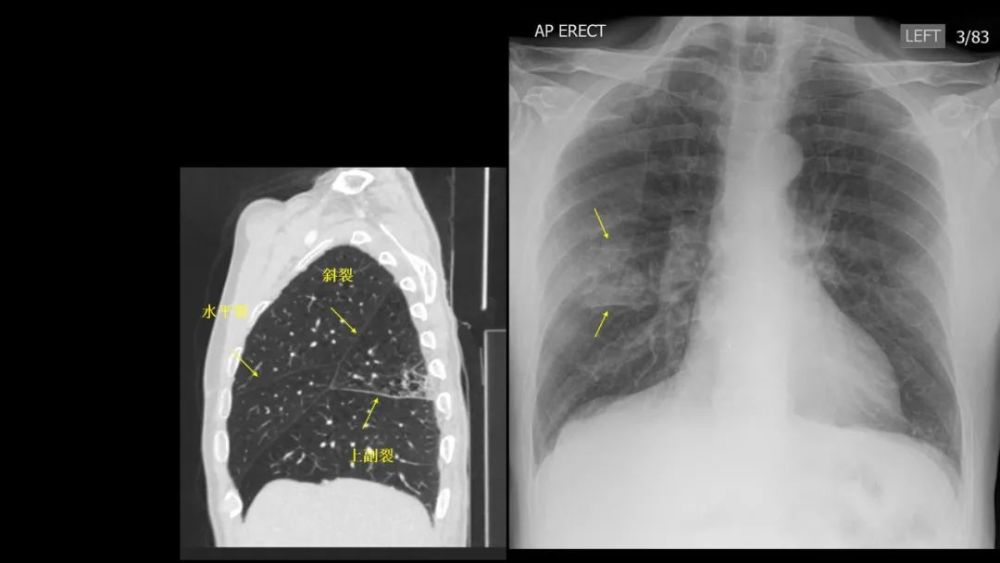

上副裂/叶

Superior accessory fissure

右肺下叶的上副叶 , 位于水平裂后方 , 将右肺下叶分为 上和基底段 , 称为后叶或背叶( posterior or dorsallobe)

可以完整或不完整 右肺多

Inferior accessory fissure

Twining’s line , 分隔下叶的内侧基底段

CT上的检出率:12% , 前位胸片显示率:5~8%R:L=5:1;多为不完整的 , 0.5~2cm